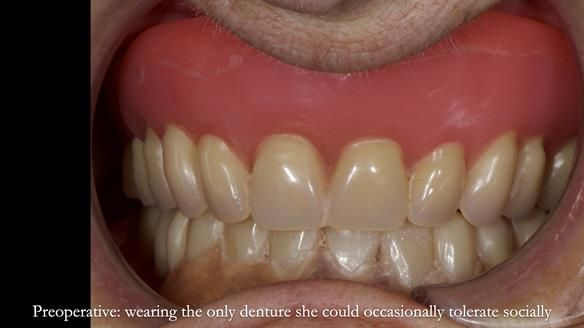

Welcome to Newsletter 83. This month I am sharing Sheila’s case — a very challenging but rewarding complete denture case. Sheila had flat ridges, a small mouth opening, a large tongue and had never been able to wear complete dentures of any kind. Everything was loose and sore. She felt embarrassed and looked older without dentures. She wanted a stable, comfortable result, and she wanted to avoid implants because she has taken bisphosphonates for more than five years.

In Sheila’s case, the Dr Abe shaped impression gave a more stable and comfortable result. Sheila preferred the shape produced by the Abe method, so that is the one we used for the registration rims, the trial denture and the final dentures. But making both impressions was worthwhile. It meant we had every option covered and could choose what worked best for her mouth.